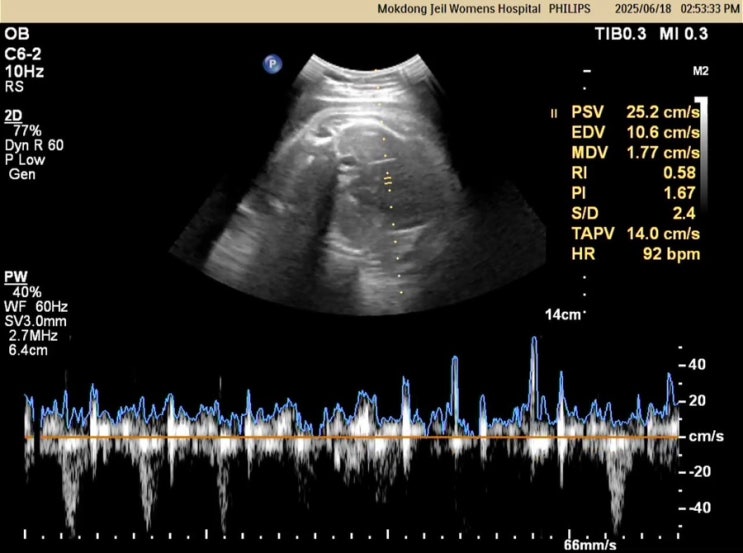

2025.06.18(출산 예정일) 드디어 출산 예정일이 되었다. 오늘도 전혀 소식이 없는 젤로 병원에 방문해서 태...